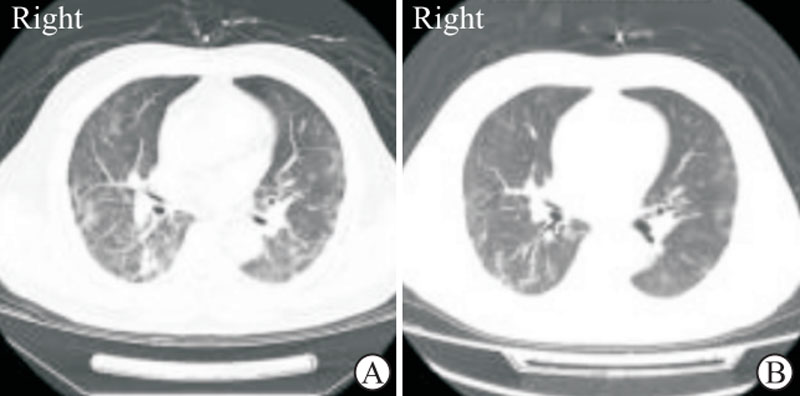

常压氧疗无法缓解进行性低氧血症的新冠肺炎患者行高压氧治疗后,肺部感染(上图)缓解、病情改善[10]。